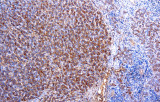

- Pannelli orientati alle entità per neoplasie linfoidi:

- Linfoma a cellule mantellari: ciclina D1 e SOX11 come marcatori chiave, incluso supporto per i casi ciclina D1 negativi.

- Linfoma di Hodgkin classico: le cellule tumorali sono tipicamente CD30+ e spesso CD15+, con PAX5 debole e CD20 negativo nelle grandi cellule tumorali.